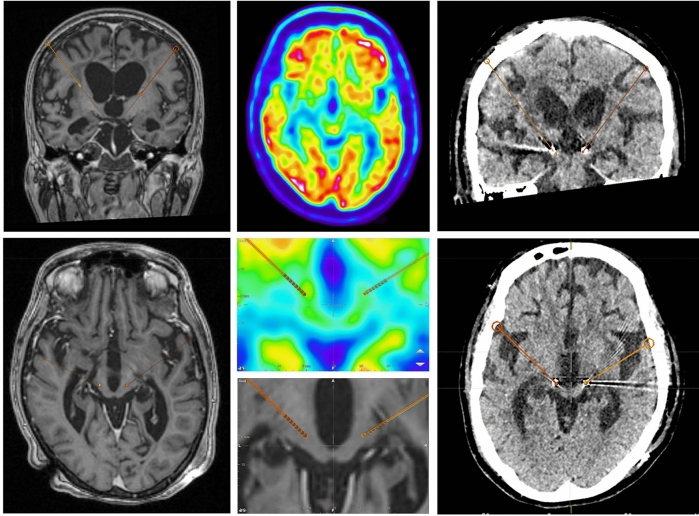

Before surgery, the patient underwent a 3T stereotactic MRI (Siemens, Malvern, Pennsylvania, USA), including axial T2-weighted and post-gadolinium (Gd) volumetric axial T1-weighted sequences. Pre-operative CM-Pf targets were determined from the mid-commissural point on anterior–posterior (AC-PC) aligned MRI images. Target planning for the central thalamus (intentionally aimed at the CM-Pf complex using traditional stereotactic methods) was optimized, based on the width of the third ventricle with final coordinates: 9.8 mm lateral, 9.5 mm posterior, and 2.8 mm ventral to the midcommissural point. Planned trajectories were inspected to be pre-coronal, start on top of a gyrus, and to avoid ventricles and blood vessels. 18F-fluorodeoxyglucose (FDG)-PET/CT brain imaging was performed on a Siemens PET/CT system (Biograph mCT FlowTrue-V-128), conform European Association of Nuclear Medicine guidelines, to confirm the presence of FDG-uptake in the center of the anticipated target area (see Fig. 4)43. More specifically, FDG images were acquired for 10 min, starting at 30 min after bolus intravenous injection, and low-dose CT was used for attenuation correction. Images were reconstructed iteratively with point‐spread function and time‐of‐flight modelling, and a 2‐mm full‐width at half‐maximum Gaussian filter. Planning, including fusion of the MRI and PET was done using Brainlab Elements software (Brainlab AG, Munich, Germany, version 3.2.0.281).

Figure 4.

Left panel: intra-operative planning MRI with trajectories. Middle panel: 18F-FDG PET-scan of target areas, including planned trajectories. Right panel: post-operative CT-scan with electrode localization.